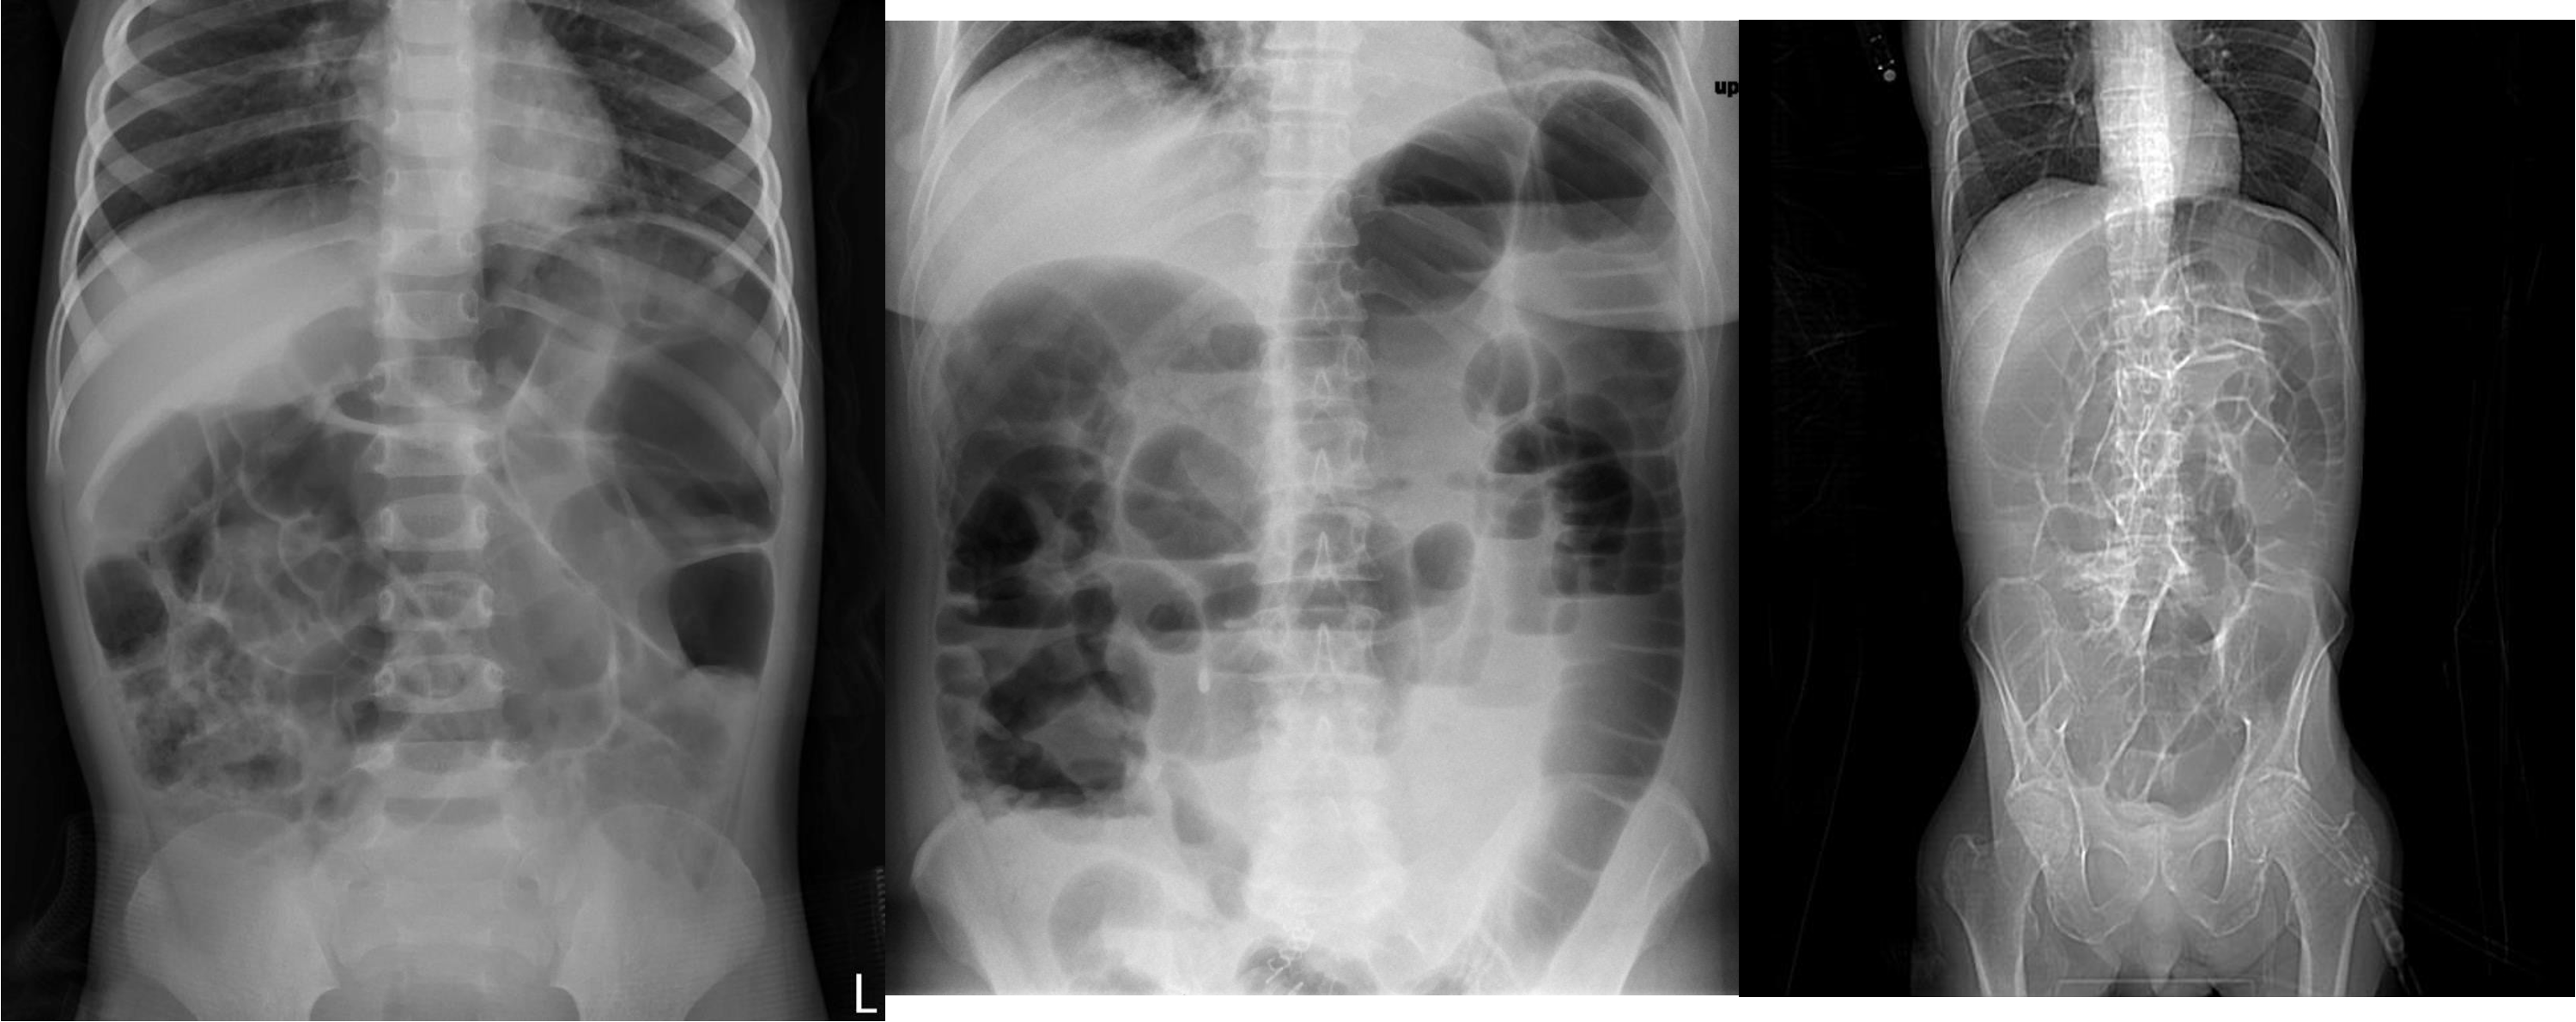

Free air under diaphragm - most commonly due duodenal perforation - (diff; perforated viscus, peptic ulcer, duodenal, penetrating truama, post surgical 8 days likely to disappear)

- free air

- erect - air fluid levels - should be not more than three - >5 significant 11 found -

- no free air under diaphgram - 8 fluid level, (evidence of bowel obstruction) (adhesion, hernia, IBD; Crohn, cancer, inturcucception, gallstones)

9 air fluids in large bowel - mucosal folds are not completed - highly suggestive of bowel obstruction

- dilated large bowel - mucosal folds are not complete - (diff; cancer, divertuclitis, volvolus, toxic megacolon?)

- if both small and large most likely nonmechanical paralytical illeus